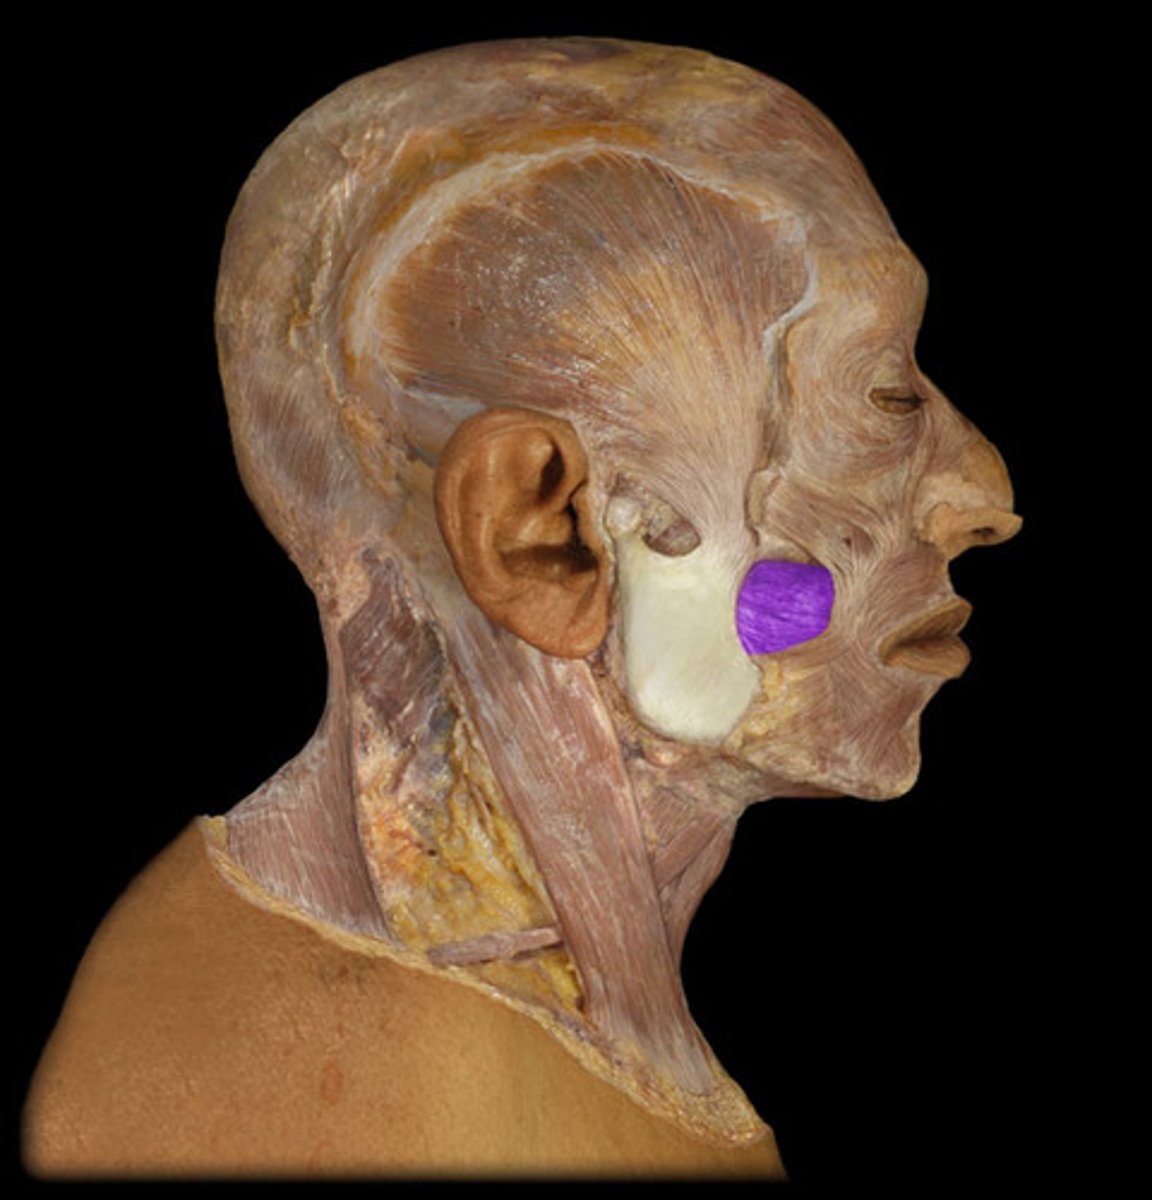

Masseter